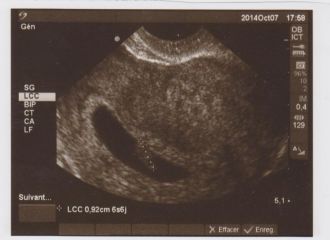

2 ème écho....

Le 7 octobre arrive.... malheureusement, mon homme n'a pas pu se libérer... je m'y rendrai donc seule...

Le RDV commence, petites questions d'usage puis, hop, écho.... la voici donc, notre petite crevette!!!! Un peu moins d'un cm et déjà, la plus jolie des images: un petit point qui clignote!!!!! <3

Si petit et déjà bien en vie! L'émotion m'envahit!

Message déposé le 16.11.2014 à 10:57 - Commentaires (2)